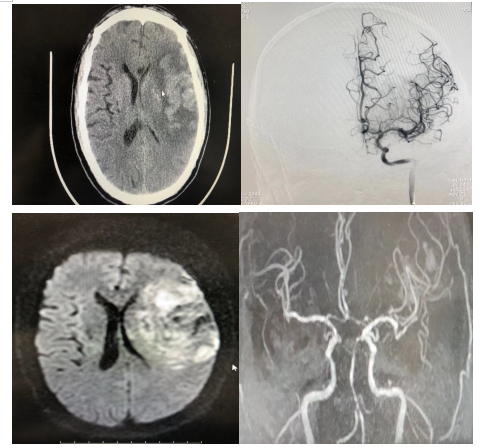

图二:术后

经过5个小时的手术,在神经内科介入团队、麻醉科的共同努力下,成功完成了首例介入下左侧大脑中动脉取栓术+左侧颈动脉C1段支架置入术。术后患者生命体征平稳,双眼无凝视,光反射灵敏,头颅CT未见出血,术后给予补液支持对症治疗,严格控制患者血压,给予替格瑞洛抗血小板对症治疗,同时加强护理,辅助拍痰,2023年3月31日患者意识逐渐转清。

经过神经内科医护团队的精心治疗与护理,患者意识清楚,右侧肢体肌力恢复为2级,无其他并发症发生,病情平稳,于4月16日出院,给予出院指导,嘱其加强康复锻炼,患者及家属对医护人员表示感谢。